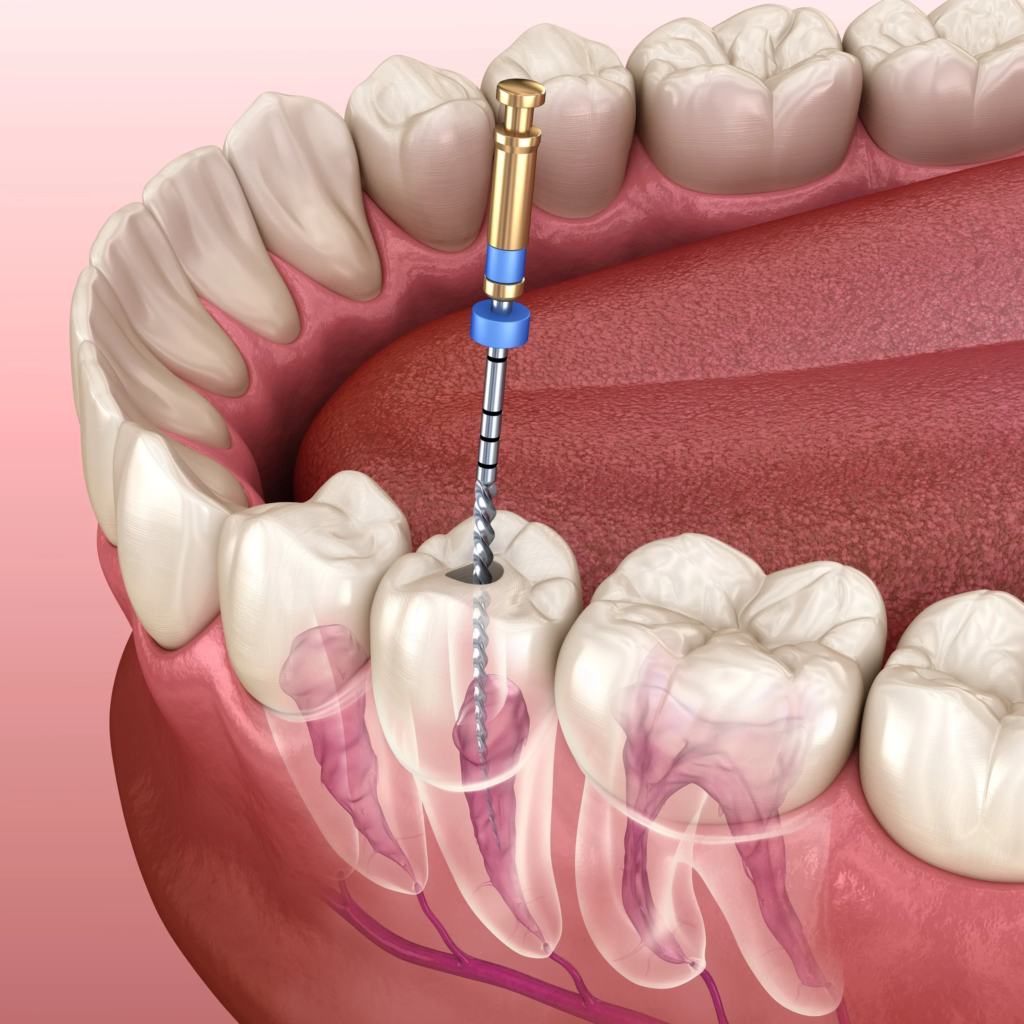

Inside each tooth is a narrow space called the root canal, which houses the pulp—a soft tissue containing nerves and blood vessels. While the pulp plays a sensory role (helping you feel hot and cold), it is not essential for the daily function of a fully developed tooth. That’s why a tooth can continue functioning normally even after the pulp is removed.

Dr. Kashfian begins by numbing the area with a local anesthetic to ensure your comfort. He then carefully removes the infected or damaged pulp using specialized instruments. Once the inside of the tooth is cleaned and shaped, the root canals are filled with a biocompatible material and sealed. A temporary filling is placed to protect the tooth until a permanent restoration—often a crown—is completed at a follow-up visit.